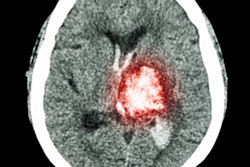

Ambulances fitted to function as mobile stroke units -- with CT, point-of-care lab testing, and thrombolysis capabilities -- improved the outcomes among patients who suffer acute ischemic stroke, according to a study published February 2 in JAMA.

Thrombolytic therapy -- dispensing drugs that dissolve blood clots in the arteries or veins -- is most beneficial when it is administered as soon as possible after a stroke occurs, Ebinger's group noted. Since there are few data on the effect of mobile stroke units on patients' functional outcomes after stroke, the researchers conducted a study using emergency calls/ambulance dispatch information from Charité between February 2017 and October 2019. The study included 1,543 patients, to whom 749 were sent both the mobile stroke unit and a conventional ambulance and to whom 794 were sent a conventional ambulance only.